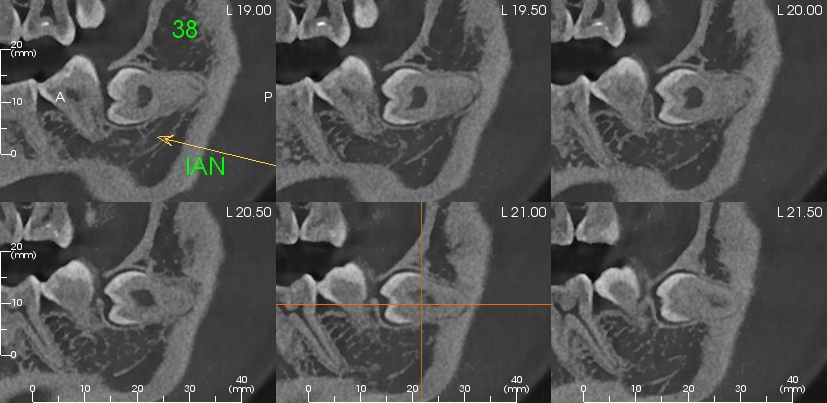

Impacted Tooth